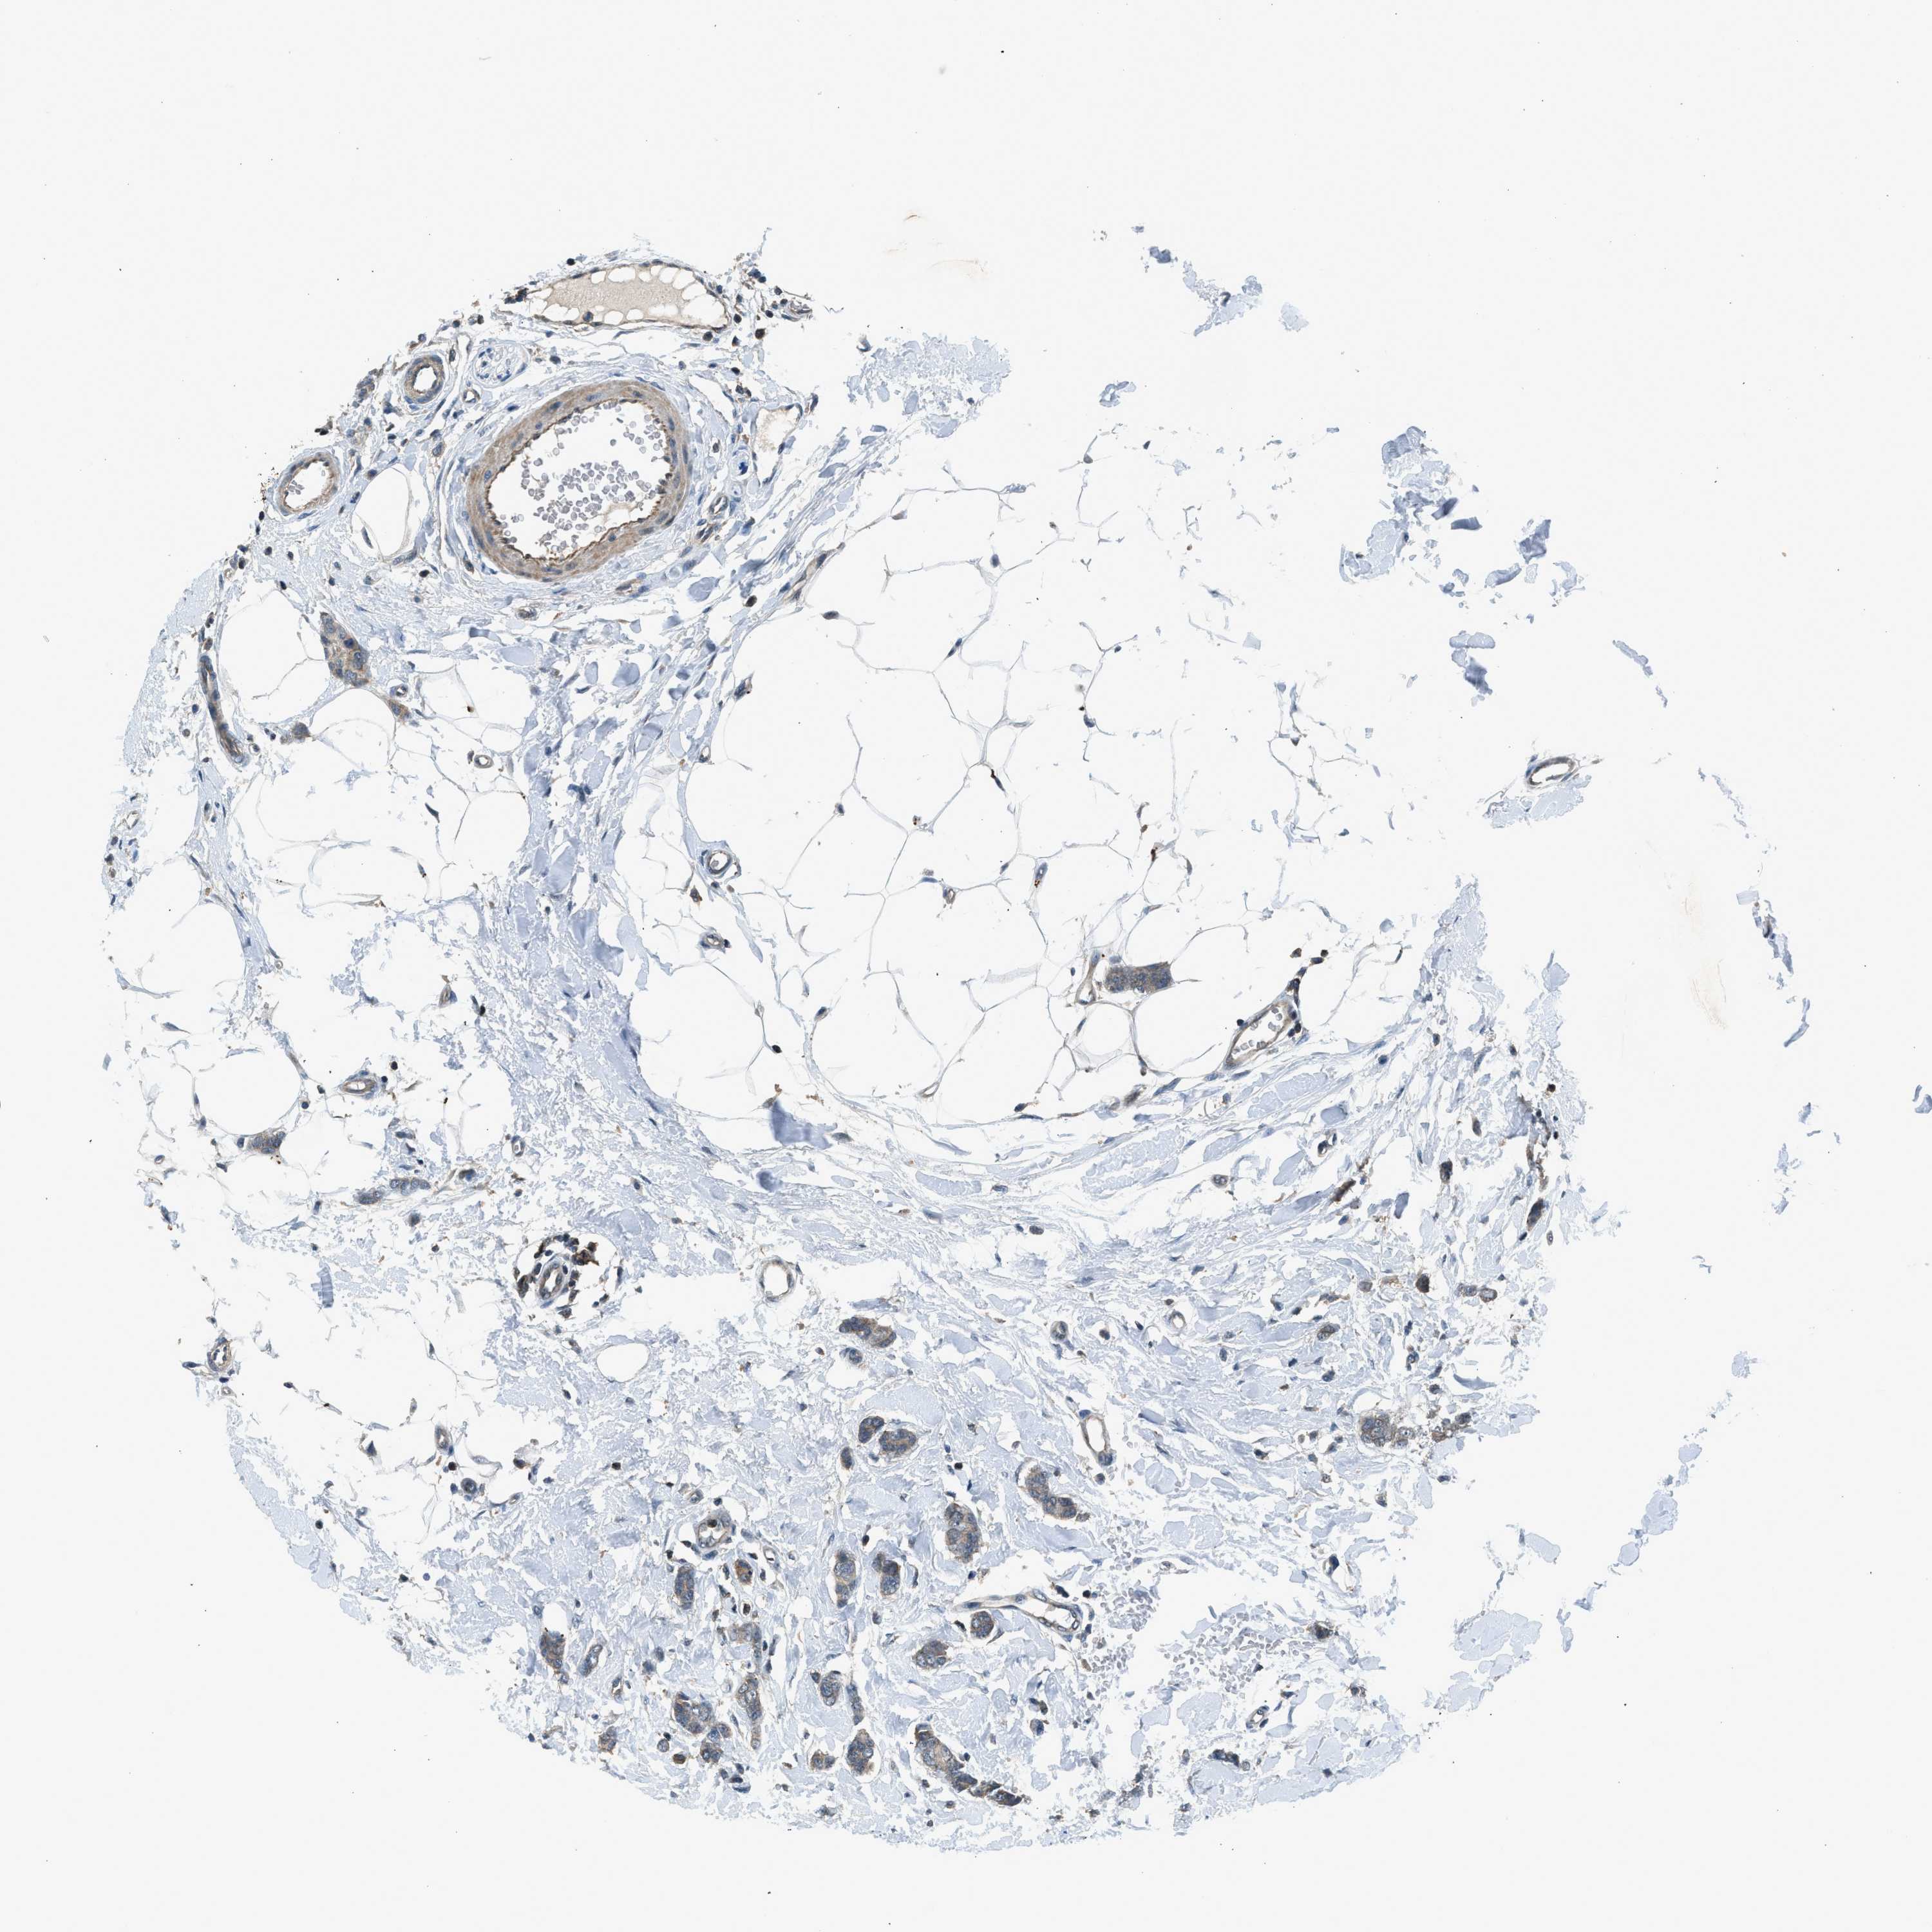

CANCER BREAST CANCER Show tissue menu

BRCA TCGA BRCA VALIDATION PROTEIN EXPRESSION